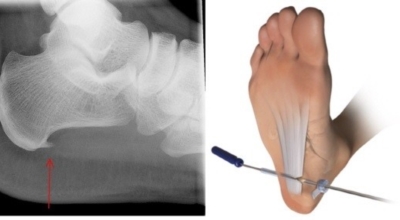

비수술적 치료로 대부분 족저 근막염 증상이 완화될 수도 있지만 일부 환자는 수술이 필요한 경우가 있답니다. 수개월간의 비수술적 치료를 했음에도 발 통증이 계속되면 수술을 고려해봐야 하며 수술을 통해 족저 근막을 늘려주는 방법을 고려해 볼 수 있다고 하네요.

최근 관절경을 이용해 족저 근막 절개술을 시도하기도 하는데 수술적 치료의 성공률은 70~90%로 높게 알려져 있답니다. 하지만 수술 후 신경 손상 등등의 합병증이 유발될 수 있으므로 잘 알아보고 전문의와 상담후 수술을 결정하시는게 좋아요.